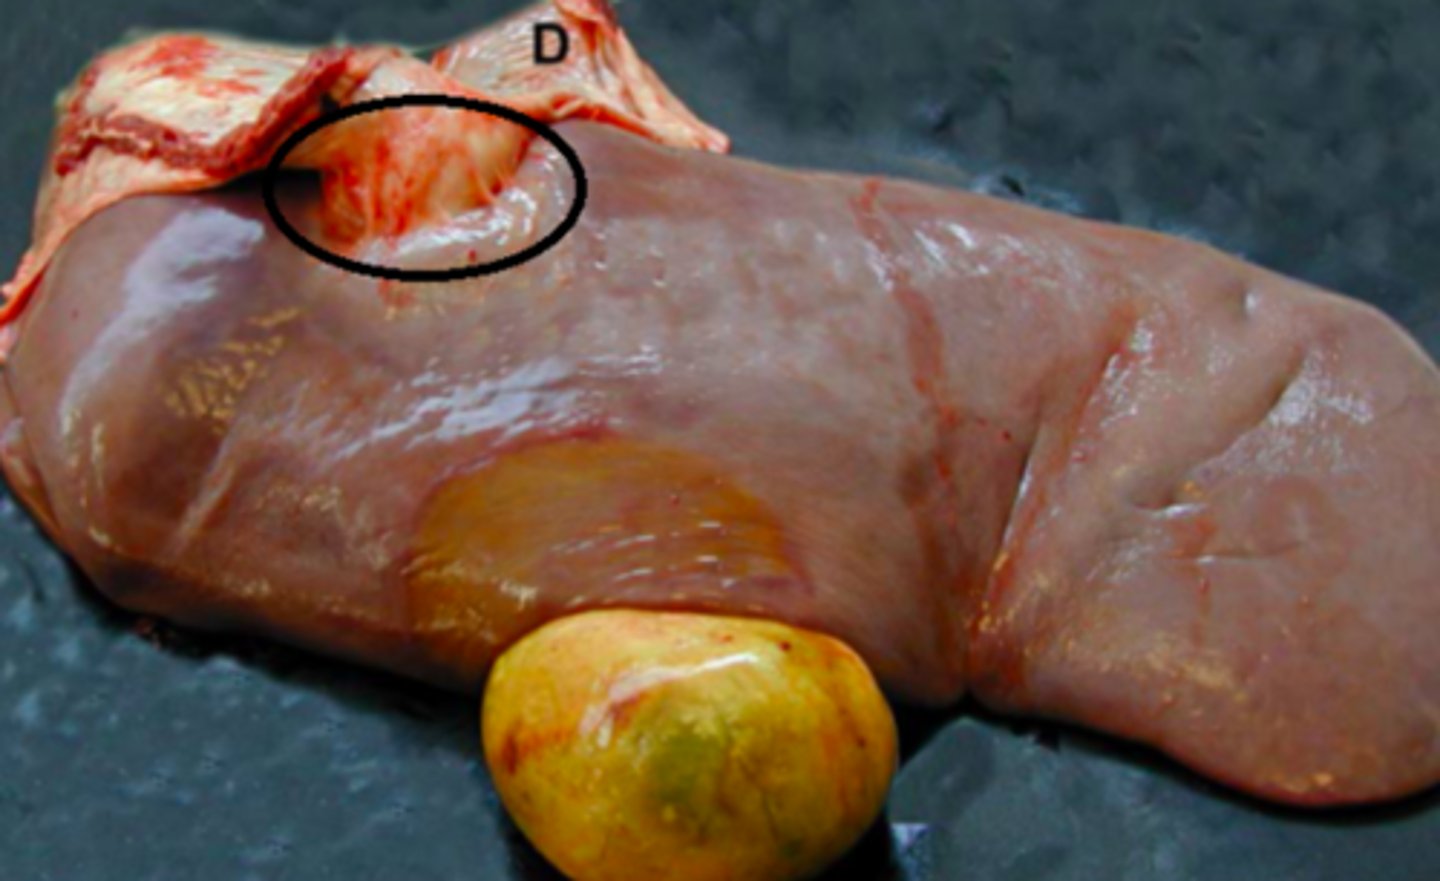

kronisk fibroniserende cholangioheptatitis (pile)

Ætiologi: Dicrocoelium dendriticum (den lille leverikte)

Lever fra får, hvad er den patoanatomiske diagnose og ætiologien?

Kronisk multifokal, fibrøs, interstitiel hepatitis

Ætiologi: migration af Ascaris suum larver

Lever fra svin, hvad er den patoanatomiske diagnose og ætiologien?

Kronisk peritoneal og perihepatisk cystecerkose

Ætiologi: Cysticerus tenuicollis

Lever fra får (med diaphragma, D), hvad er den patoanatomiske diagnose og ætiologien?